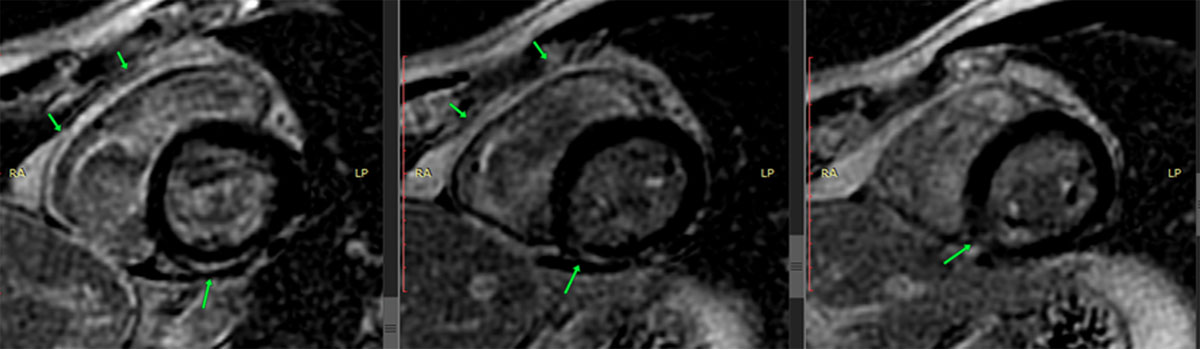

The presence of myocardial edema was also observed in the same inferior wall with inferoseptal extension (Figure 4). Late enhancement sequences revealed gadolinium uptake in the basal, medial, and inferior basal inferoseptal segments of the left ventricle, and the pericardium in its basal region (Figure 5). All of these findings are consistent with acute myocarditis.

Figure 5

Cardiac MRI with late gadolinium enhancement in the inferoseptal, inferior, and inferomedial segments.